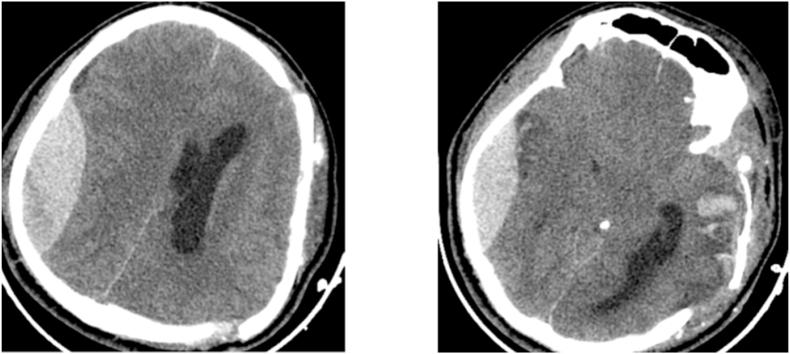

A 30-year-old patient with no past medical history, was brought to the emergency after a severe brain injury secondary to an aggression, Glasgow coma scale was 6 (E1V1 M4) with a left anisocoria. The CT scan revealed a left acute subdural hematoma with midline shift superior than 10 mm, and a non-surgical contralateral EDH was also identified. The patient was operated on urgently. Post-operatively, the pupils became equal sized and reactive. A right anisocoria was noticed 12 h later, with a large contralateral EDH on CT scan associated to a gross midline shift. A second operation was performed immediately with a good recovery and the patient was extubated one week post-operatively.

一名30岁无既往病史的患者,在因暴力导致严重脑损伤后被送往急诊室,格拉斯哥昏迷量表评分为6分(E1V1M4),伴有左侧瞳孔不等大。CT扫描显示左侧急性硬膜下血肿,中线移位超过10mm,同时还发现对侧非手术性EDH。患者紧急接受手术。术后,瞳孔大小恢复正常且有反应。12小时后发现右侧瞳孔不等大,CT扫描显示对侧有巨大EDH并伴有明显中线移位。立即进行了第二次手术,恢复良好,患者术后一周拔管。